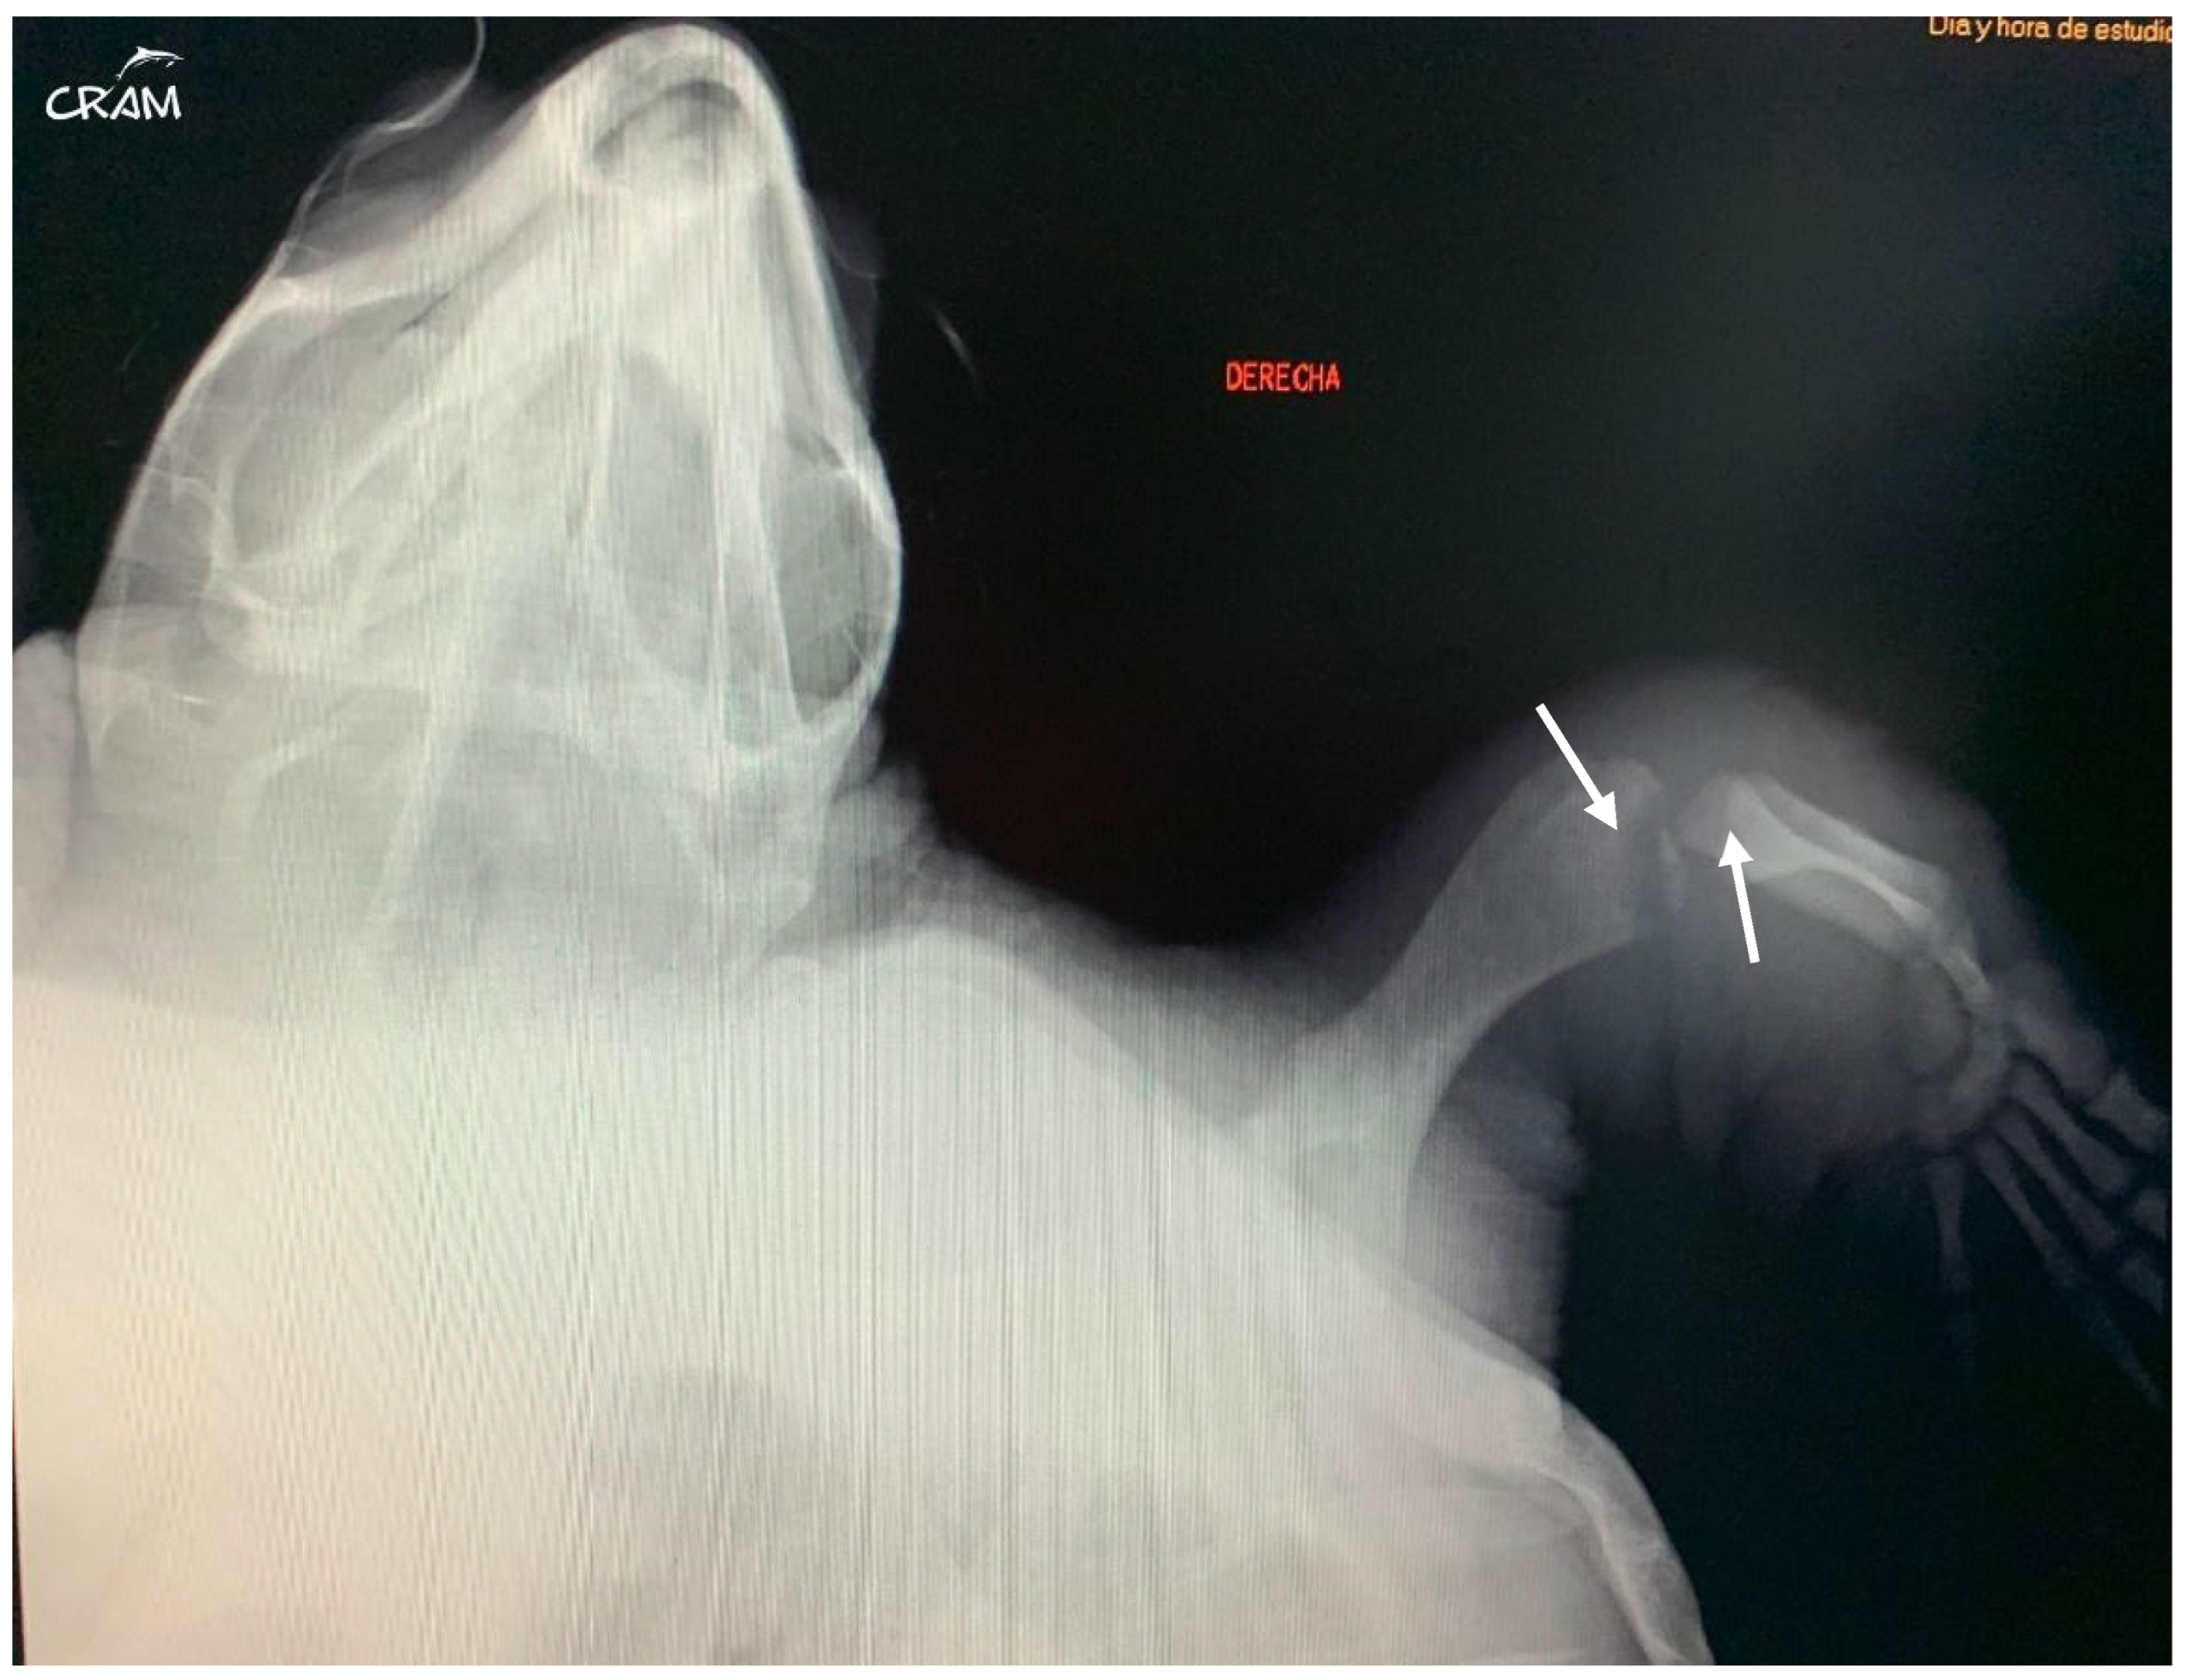

Hard edema with increased periarticular soft tissue and pain was noticed at palpation during clinical evaluation in veterinary medicine [21]. At the beginning of signs, radiographic lesions were polyostotic and poorly defined (Figure 5 and Figure 6).

Figure 5.

Dorsoventral radiograph of the right front flipper at day 45 of rehabilitation. Well-defined bone lesions (arrows) are noted. Lesions are lytic with relevant osteopenia and no bone remodeling. The lytic process is seen communicating with the joint space in the elbow joint.

Early-stage lesions at day 45 of rehabilitation were characterized by a purely osteolytic process restricted to the distal end of the humerus and femur and the proximal end of the radius, ulna, and tibia, including demineralization of the surrounding bones. Osteolytic lesions were restricted to the epiphysis and metaphysis of long bones, and no lesions were detected in the diaphysis.